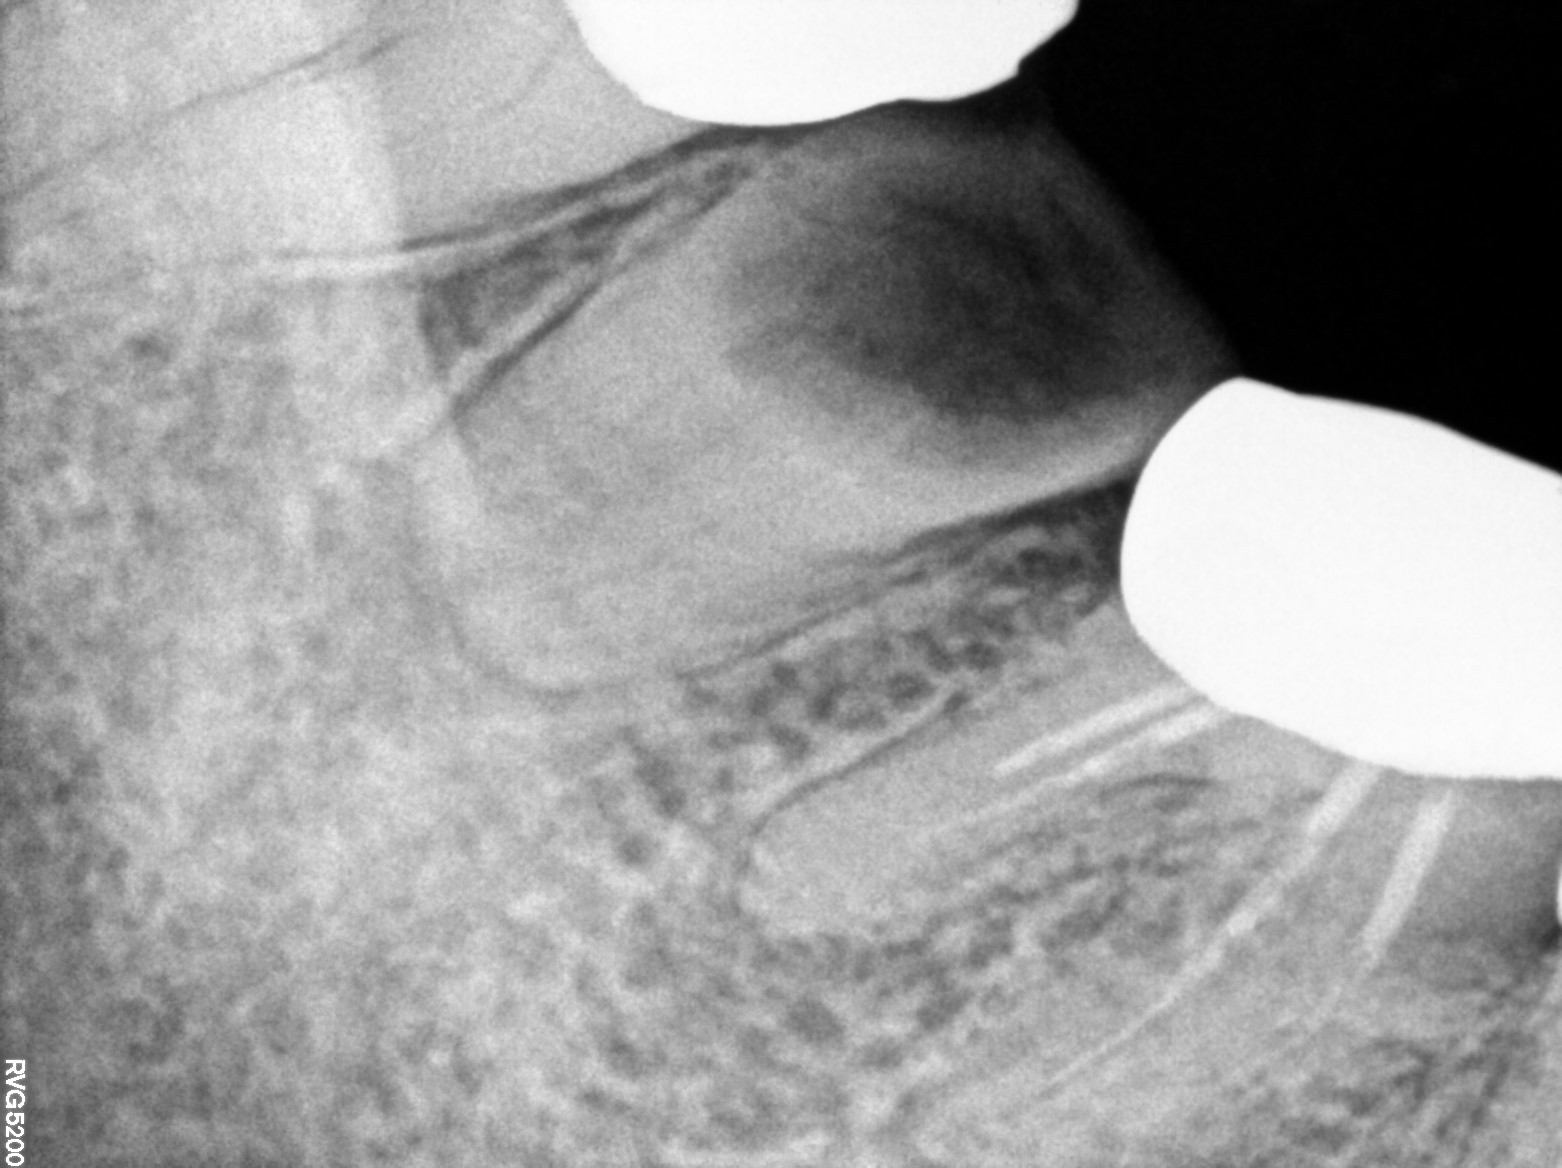

Dental Radiographs FHIR: DocumentReference · LOINC 24641-7

d (16).jpg

24641-7